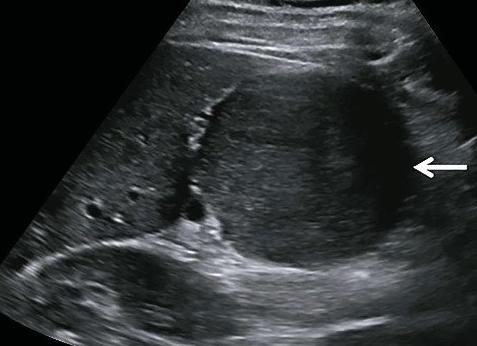

Гипоэхогенное образование – это патологический очаг на печени, который имеет меньшую нежели у органа плотность. Когда УЗ волны проходят через этот участок они замедляют свою скорость. На мониторе аппарата – это будет показано как более темное пятно, нежели остальной орган. Такие новообразования – это сигнал о развитии патологических процессов, вероятнее разрушительный процесс.

Итак, начнем с понятия, что такое гипоэхогенное образование в печени на УЗИ (синоним гиподенсивное) — это участок с более низкой плотностью в ткани органа. Как правило, на мониторе УЗИ гипоэхогенная зона выглядит в виде темного пятна. Часто так выглядит киста, либо ее разновидности, представляющие собой образование, полость которого заполнена жидкостью.

Темное пятно на УЗИ — очаг пониженной плотности, свидетельствующий о заболевании и наличии патологий в органе.

Структуры органа, имеющие разную плотность и строение, по-разному отражают эти волны, которые возвращаются обратно, фиксируются особыми датчиками аппарата УЗИ и формируют картину состояния органа. Если в структуре органа имеется образование или участок с более низкой плотностью, чем другие части или ткани, оно будут выглядеть на экране УЗИ как гипоэхогенное образование в печени.

Обследование на УЗИ позволяет не просто определить наличие таких образований, но и узнать их месторасположение, количество и размеры. На экране гипоэхогенная зона выглядит как темное пятно. Чаще всего в роли таких образований выступает участок ткани в виде полости, заполненной жидкостью. Она обычно бывает окружена тонкими стенками, отделяющими ее от соседних тканей. У нее могут быть гладкие ровные края или же неровные очертания.